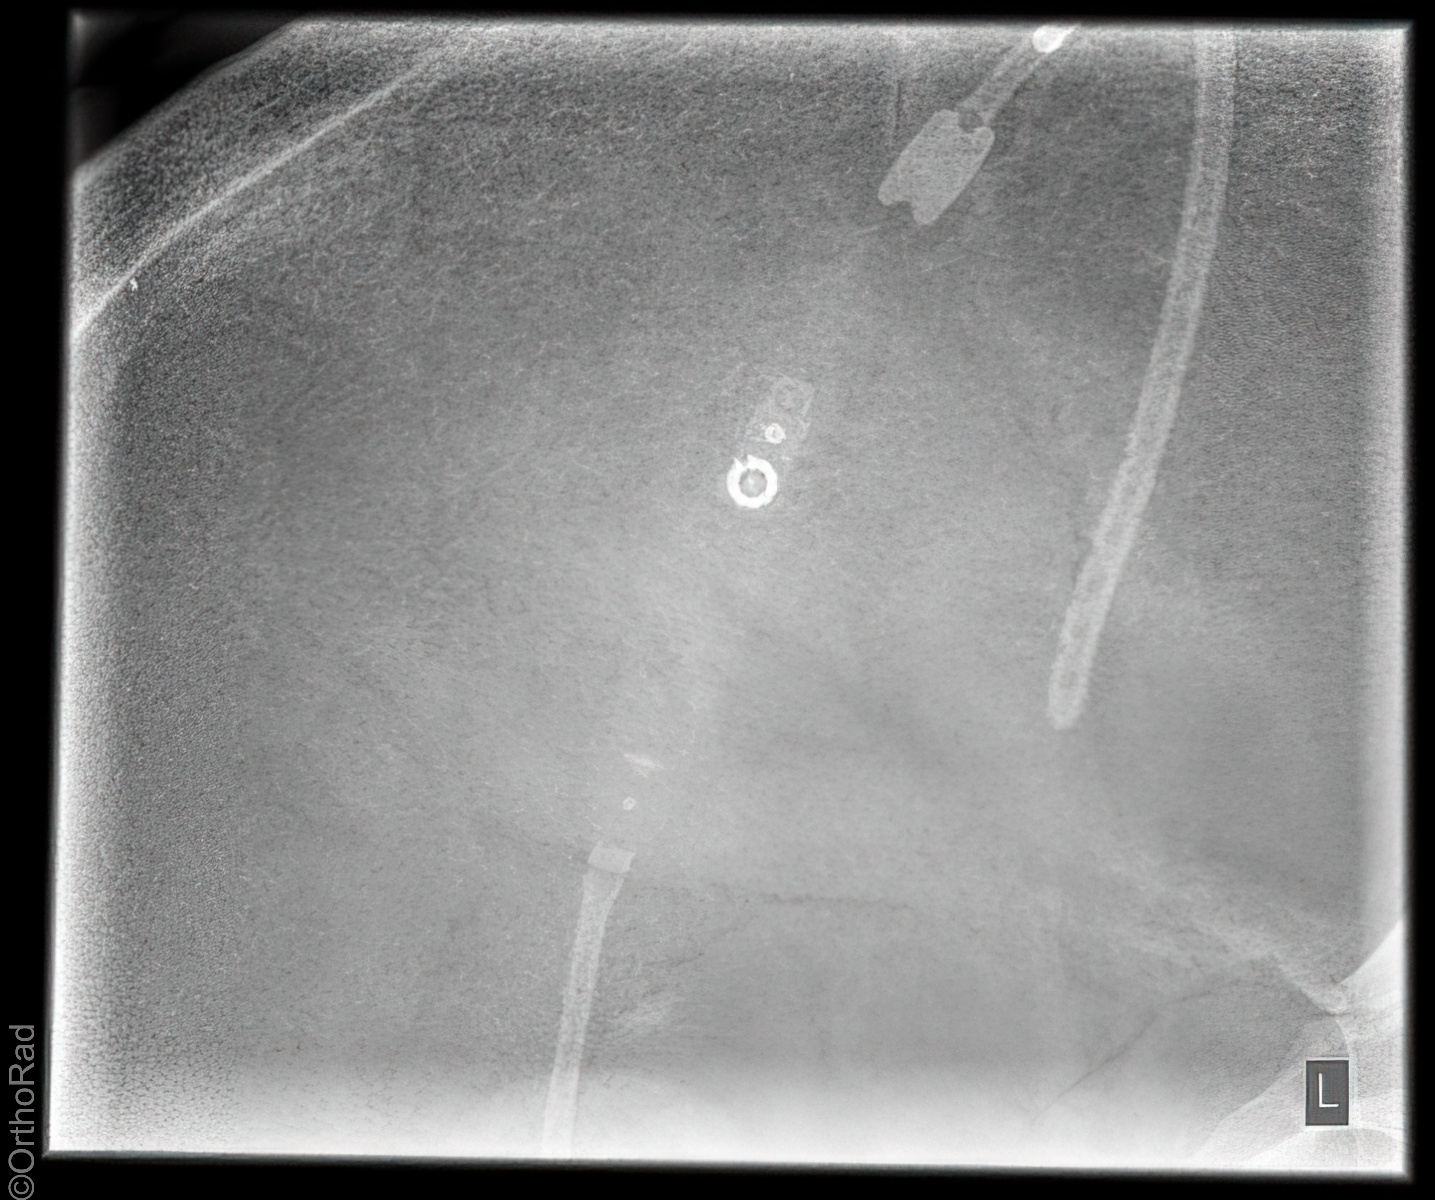

Shuntverlauf

Es wurden keine Bilder gefunden.

Technik

FDA: 1,15 m

Ausgangsformat: je nach Körperregion

mit Raster

Indikation

Shuntkontrolle

Lagerung

1. Schädel/HWS ap

Patient in Rückenlage, Kinn anziehen lassen, 15° Keil unter den Kopf, so dass Deutsche Horizontale (DH = Frankfurter) senkrecht zum Film steht, Kopf muss seitengleich, symmetrisch gelagert werden.

2. Schädel/HWS seitlich

Patient in Rückenlage, Kopf auf die rechte Seite drehen und Medianebene verläuft parallel zum Tisch, Stirn-Augenbrauen-Linie verläuft senkrecht und die Stirn-Kinn-Punkte verlaufen parallel zur Filmeinblendung. Der Körper dreht sich somit etwas auf die rechte Seite.

3. Thorax/Abdomen

Patient in Rückenlage, Arme am Körper entlang, Beine geschlossen.

4. evtl Becken

Patient in Rückenlage, Beine leicht gespreizt.

Zentralstrahl

Senkrecht auf Objekt, vom Schädel bis Abdomen müssen alle Bilder überlappend sein.

Variante

Abdomen evtl seitlich röntgen, wenn die Shuntlänge 3-4cm unterhalb der Markierung ist (nicht mehr im kleinen Becken) -> Belichtung dann wie seitliche Wirbelsäule.

Anmerkung

Die Stelle (Narbe) an der der Shunt in dem Abdomen verschwindet, muss mit einer Metallkugel etc. markiert werden.